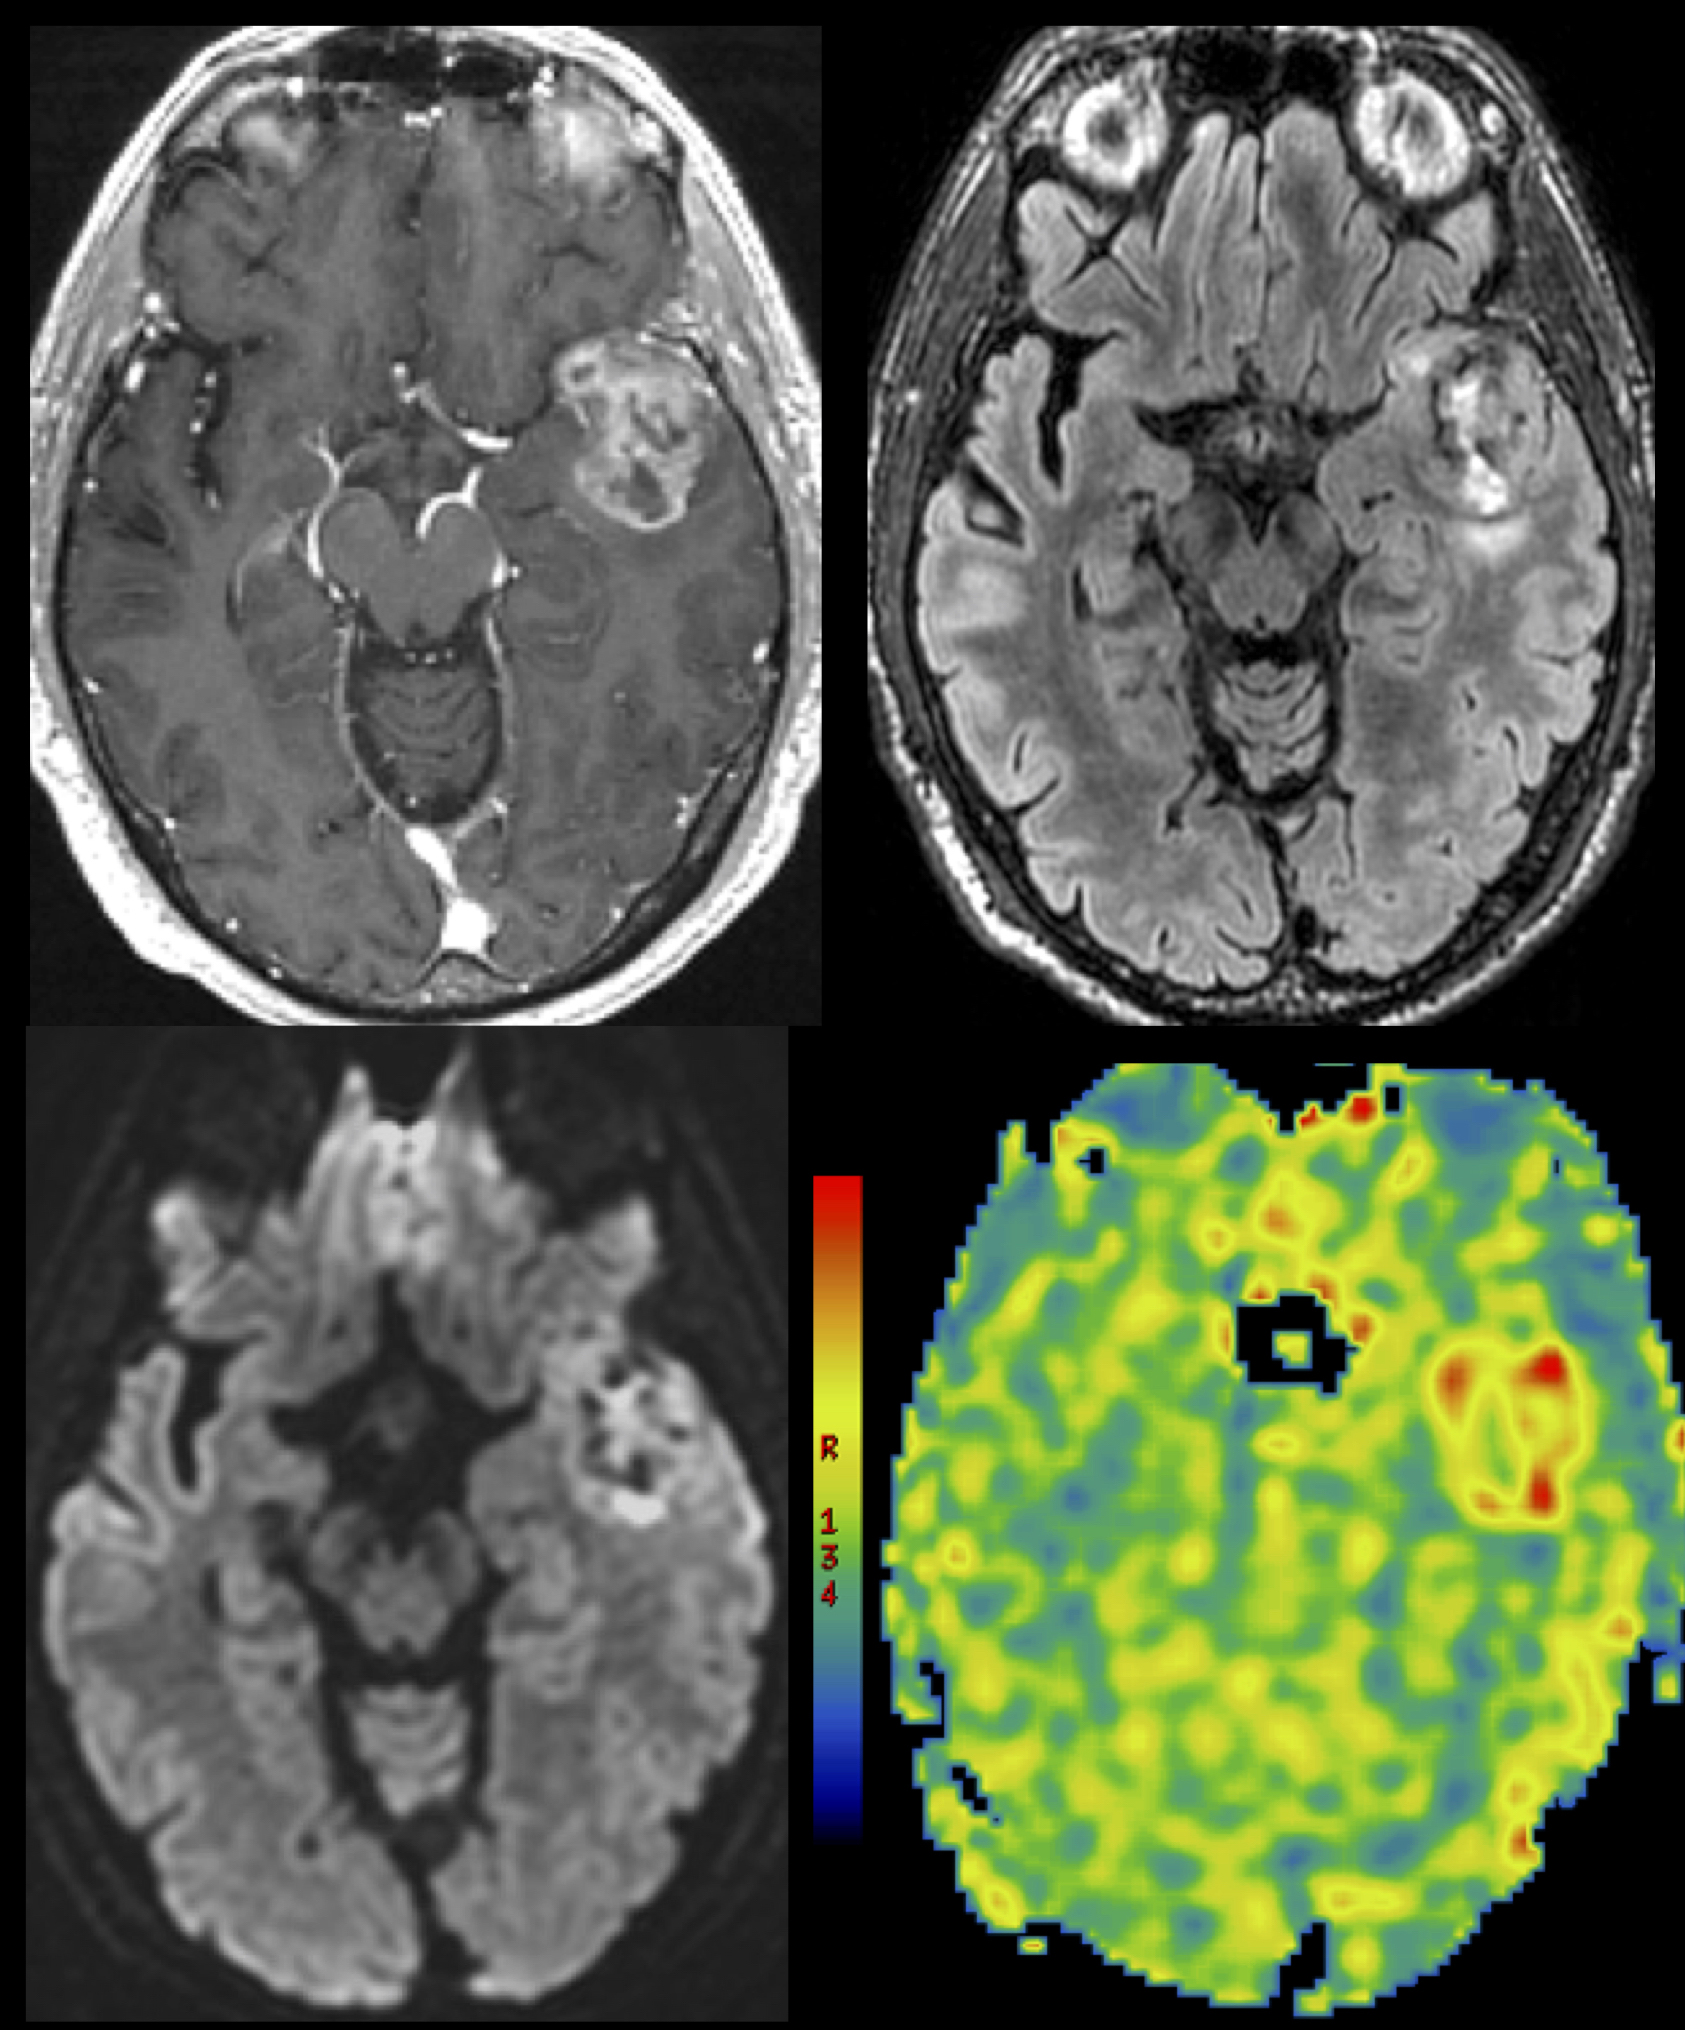

Radiology plays an integral role in the diagnosis, treatment planning, and monitoring of brain tumors. Every day, brain tumor patients visit the UCSF Department of Radiology and Biomedical Imaging for MR imaging. For patients, these visits are often emotional events as the imaging findings determine the course of their care. At UCSF, neuroradiologists interpret each scan in the context of the patient’s pathology and therapy. And, in addition to conventional structural MR imaging, we routinely incorporate biology-driven MR imaging techniques. On the biomedical imaging front, UCSF researchers are working to incorporate multiparametric and molecular imaging techniques to mirror advances in brain tumor genetics that will allow doctors to better understand tumor pathophysiology and deliver tailored therapy.